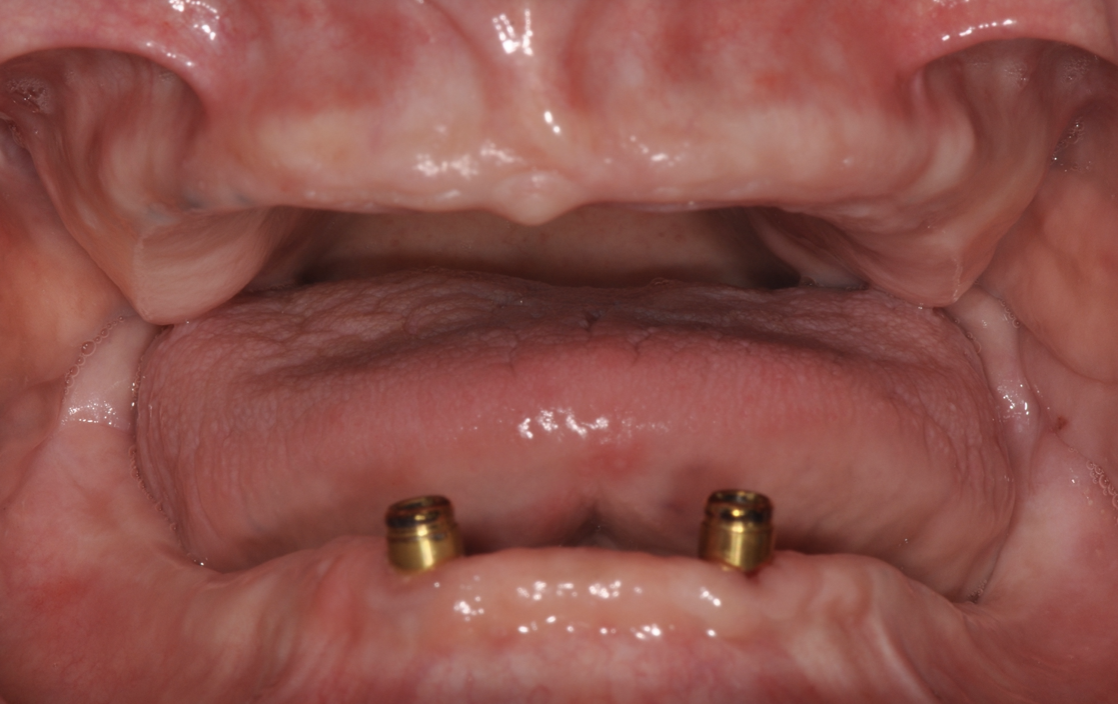

精於贗復補綴專科,4D數位重建、植牙美學、全瓷美齒,重視醫病關係享譽醫學界精於贗復補綴專科,4D數位重建、植牙美學、全瓷美齒,重視醫病關係享譽醫學界,精於贗復補綴專科,4D數位重建、植牙美學、全瓷美齒,重視醫病關係享譽醫學界。

透過初診獲得的檢查資料,在電腦內進行牙齒及模型分析,以設計未來活動假牙最佳的支撐位置與咬合狀態。 ●正式假牙 精細修磨牙齒並用數位方式取得正式模型,此步驟取代傳統印模方式,大幅減少材料流動造成的不適感。接著用3D列印/電腦切削方式製作正式假牙。 ●口內試戴 試戴活動假牙支架及排牙蠟型,確保可精準貼合牙齒,以達到美觀及咬合需求。